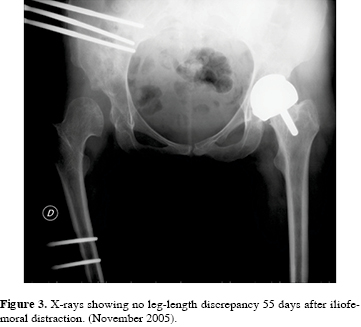

In October 2005 a capsulotomy through lateral approach was performed and an iliofemoral external fixator (Orthofix, Bussolengo, Verona, Italy) was implanted using three hydroxyapatite coated pins16 on the lateral aspect of the iliac wing and two pins inserted into the femoral diaphysis with no distraction at the time of surgery. Percutaneous adductor tenotomy was performed to achieve further soft-tissue distraction. Postoperatively, progressive one mm distraction per day was planned, until the tip of the greater trochanter reached the upper border of the native acetabulum (Figura 3). External fixator was well tolerated by the patient, with no signs of pin tract infection. After 55 days, the external fixator was removed, and through the same lateral approach, a HR was implanted (42-mm cemented femoral head, 50-mm uncemented acetabular cup). The acetabular shell was positioned with an inclination of 47o. The limb-length discrepancy was completely restored.